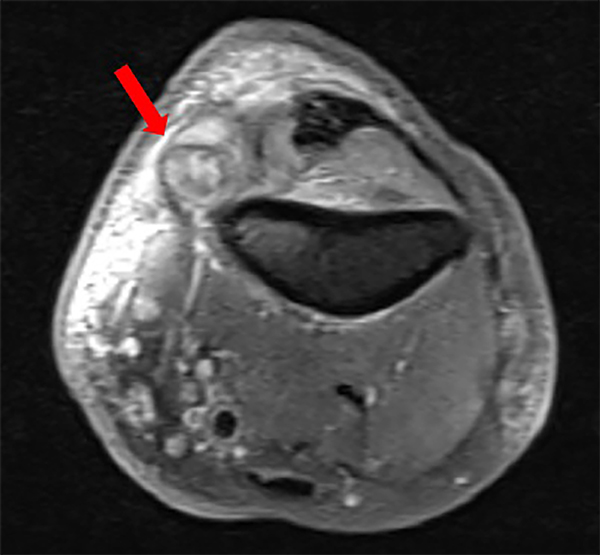

Se realiza Resonancia Magnética de MSI con cortes ponderados en T1 y secuencias STIR, que evidenció un proceso patológico a nivel de codo, en íntima relación con nervio cubital en su trayecto en el conducto epitrócleo-olecraneano, con características quísticas secundarias a proceso inflamatorio/infeccioso cronificado (Figura 4).

Figura 4: Resonancia Magnética de MSI con cortes axiales ponderados en secuencia STIR, donde se observa un proceso patológico con características quísticas a nivel del conducto epitrócleo-olecraneano. En la flecha se logra visualizar el engrosamiento del nervio mediano.